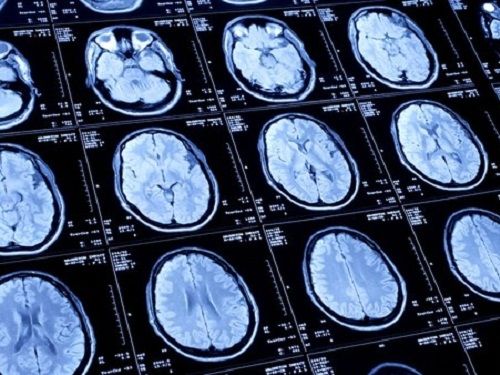

Connaissance du cerveau, lancement officiellement de l’institut CESAME de Lyon

Dix jours après la fin de la semaine nationale du cerveau, la Fondation Neurodis à officiellement lancé la premières technologique des cinq plates-formes consacrées aux signaux intracérébraux, sur le site de l'Hôpital Neurologique de Lyon et qui sera entièrement dédiée à l'épilepsie pharmaco-résistante. Au final ce sont cinq plateformes de haute technologie qui composeront CESAME qui seront intégralement mises en place d'ici juin 2014. Quatre plates-formes dédiées à l'ingénierie cellulaire et optogénétique, à l'imagerie anatomique et fonctionnelle cérébrale, à l'environnement virtuel et neuro-immersion pour la rééducation fonctionnelle, enfin une barrière hémato-encéphalique et biodisponibilité des médicaments

En Europe, une personne sur trois est frappée d'une pathologie en lien direct ou indirect avec le cerveau et ceci à tous les âges de la vie. Selon l'Organisation mondiale de la santé, les maladies du cerveau représentent 35% des coûts de santé publique. L'Institut CESAME de Lyon répond à ce défi majeur. Il se concentre sur un rapprochement entre les connaissances du cerveau, les maladies cérébrales et les activités mentales, opérant ainsi une réelle ouverture des Neurosciences à la santé mentale et, plus largement, à la société.

CESAME s'appuie sur des compétences internationalement reconnues et diversifiées. Soutenu par les mondes académique, hospitalier et industriel, l'Institut CESAME dispose de tous les atouts pour la création d'un pôle d'excellence hospitalo-universitaire apte à développer des thérapies innovantes rapidement transférables vers la pratique médicale. Il fédère d'ores et déjà un tissu industriel désireux de s'associer à sa démarche de valorisation économique.

Totalement opérationnelle depuis janvier 2013, la première plateforme de l'Institut CESAME consacrée aux signaux intracérébraux est installée dans le service de neurologie fonctionnelle et d'épileptologie de l'Hôpital neurologique de Lyon. Elle est dédiée à la recherche sur les mécanismes fondamentaux de fonctionnement du cerveau humain et à leurs perturbations dans l'épilepsie. Concrètement, cette plateforme permet de réaliser des enregistrements de l'activité électrique du cerveau humain chez des patients souffrant d'épilepsie réfractaire et pour lesquels il est nécessaire d'implanter des électrodes intracérébrales dans un but de traitement chirurgical.

Un matériel dédié à l'électro-encéphalographie (EEG) intracérébrale permet l'enregistrement de 256 canaux avec une fréquence d'échantillonnage pouvant atteindre 2048Hz. L'année 2013 sera consacrée à la mise au point d'enregistrements par microélectrodes permettant d'accéder à l'analyse de l'activité ? Électrique à l'échelle du neurone, ouvrant ainsi de nouvelles perspectives sur la compréhension, à la fois de la physiologie cérébrale et des processus pathologiques sous-tendant la maladie épileptique. Pour ces enregistrements, des fréquences d'échantillonnages culminant à 30 kHz seront disponibles.